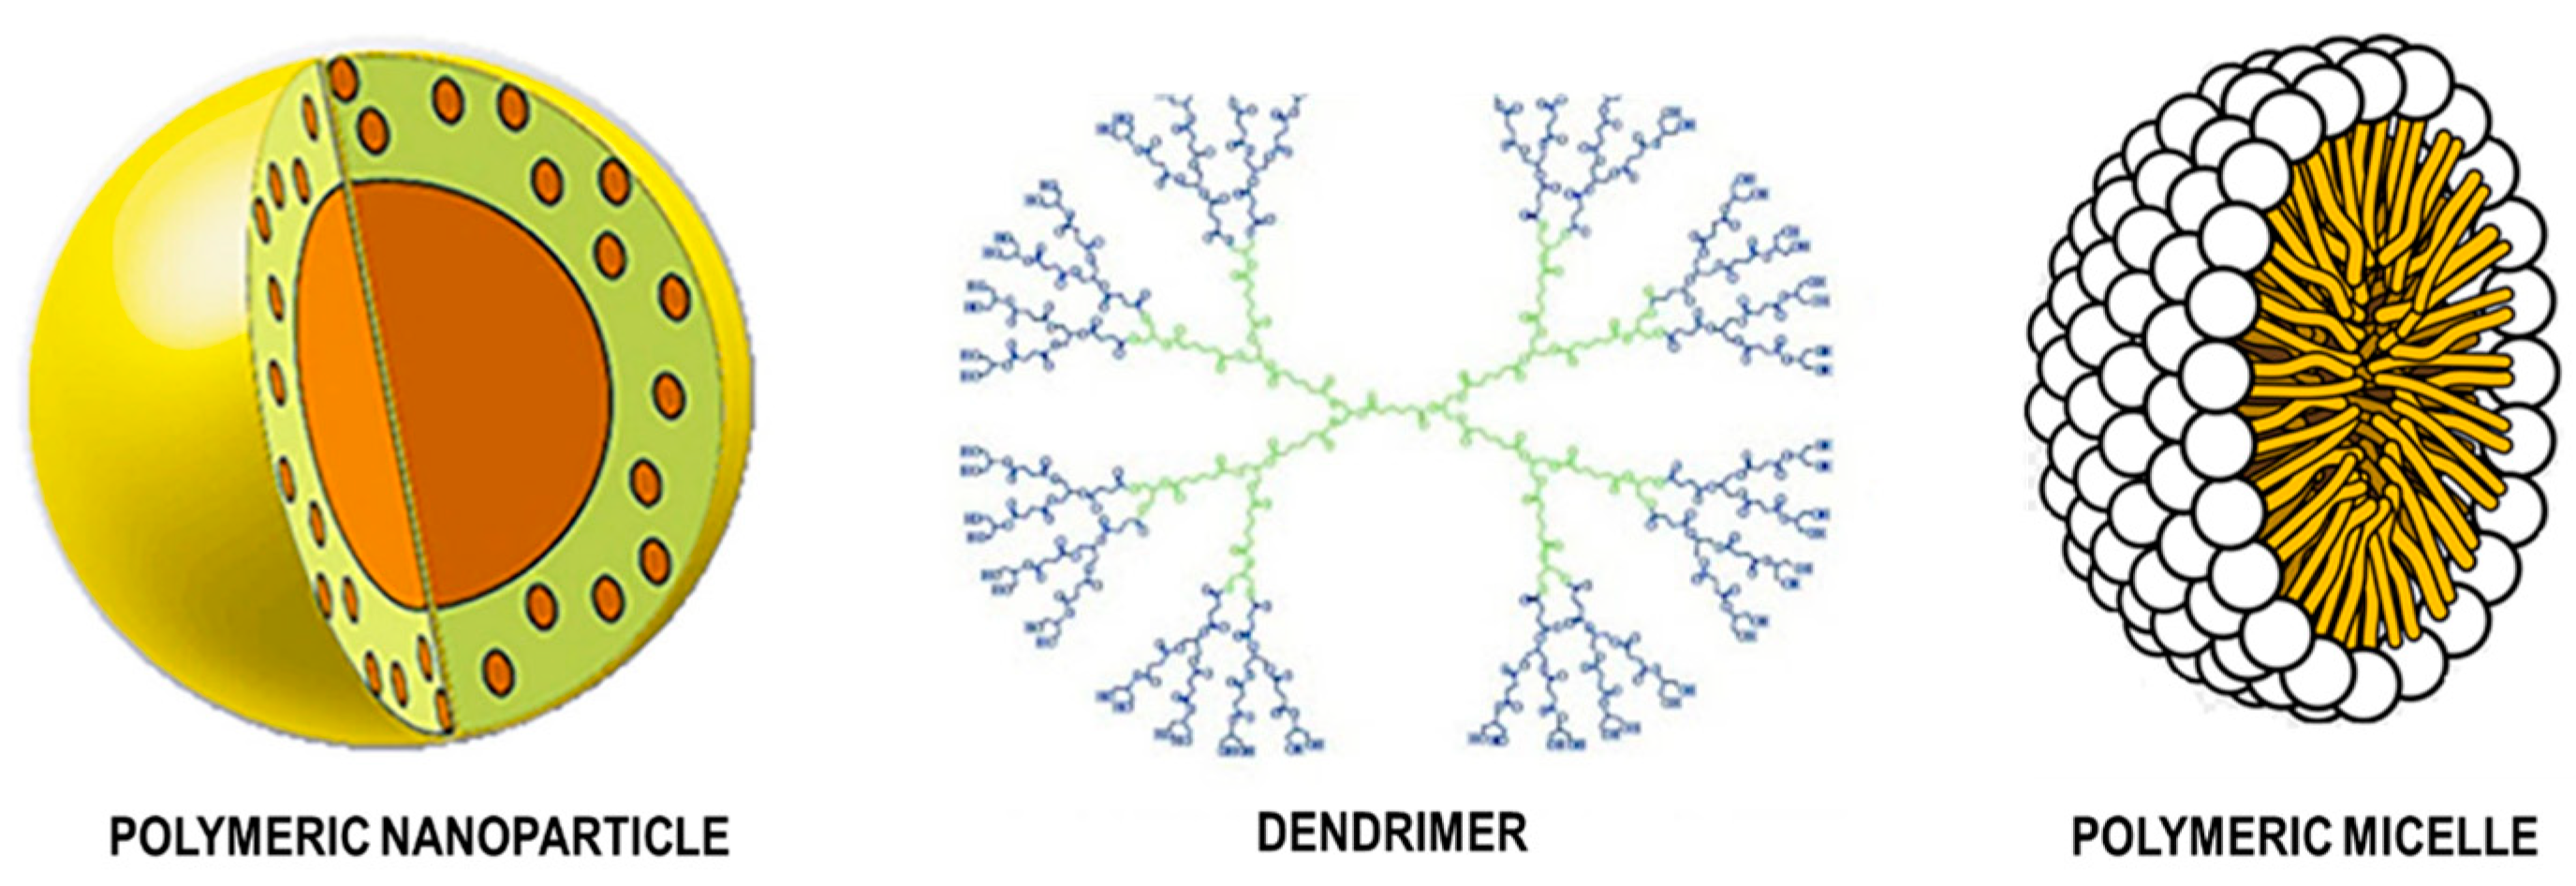

7.3. Polymer Nanoparticles

7.3.1. Natural Polymeric Nanoparticles

7.3.2. Synthetic Polymeric Nanoparticles

7.4. Inorganic Nanoparticles